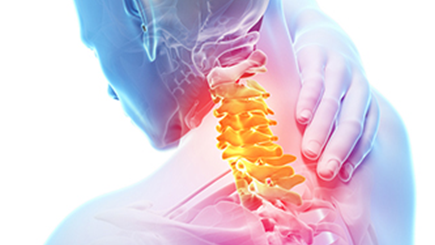

경추 내부 수액이 빠져나오며 신경근, 척수를 누르며 통증이 발생합니다. 퇴행성 변화, 사고, 잘못된 자세의 습관화가 목디스크의 주요 원인입니다.